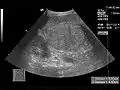

الفحص السريري للكبد يمكن أن يحدد حجمه ووجود المضض فقط، وقد تكون هناك حاجة أيضاً إلى بعض أشكال التصوير مثل الموجات فوق الصوتية أو التصوير المقطعي المحوسب.[51]

في بعض الأحيان يكون من الضروري إجراء خزعة للكبد، وأخذ عينة من الأنسجة من خلال إبرة يتم إدخالها عبر الجلد أسفل القفص الصدري مباشرة. يمكن أخذ الخزعة بتوجيه الموجات فوق الصوتية.[52]

تصوير بالموجات فوق الصوتية، تظهر كيسة كبدية.